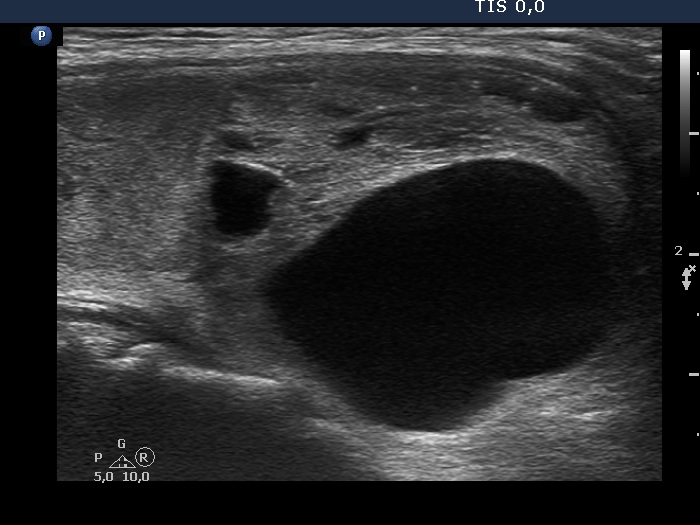

The composition of the nodule - case 1295 (ultrasonographic picture 5)

Lower part of the right lobe, longitudinal scan. In this image the solid part is followed as a thin echonormal parenchyma even in the dorsal part of the lobe which proves that this nodule is in fact a central type cystic nodule.